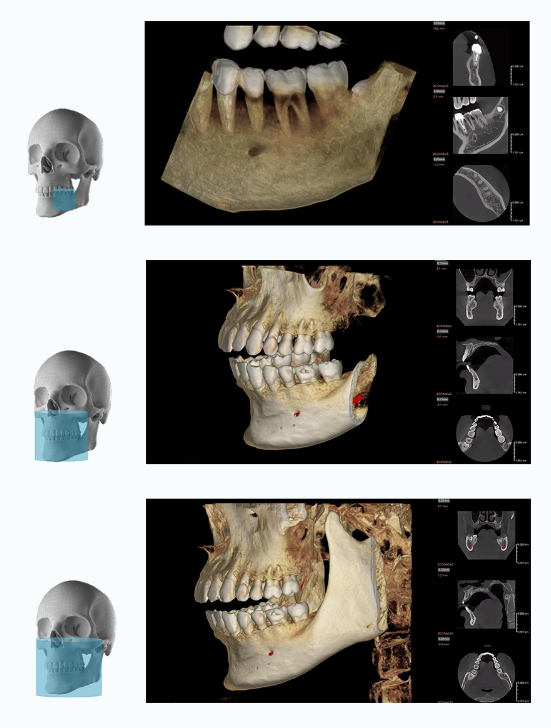

Les volumes disponibles à la fois sur Rubik X1 et RUBIX X3

5 x 5 cm / 9 x 9 cm / 12 x 10 cm

OPTIONS EXCLUSIVES DE CHAMP DE VISION DU RUBIK X1

16 x 10 cm / 16 x 16 cm